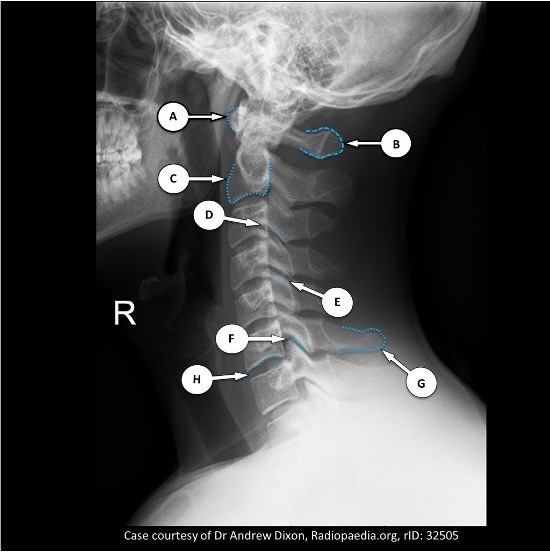

Q

Name all of these A-H

a) anterior arch of atlas

b) posterior arch of the atlas

c) body of C2

d) inferior articular process

e) superior articular process

f) zygapophyseal (facet) joint

g) spinous process of C6

h) intervertebral disc space